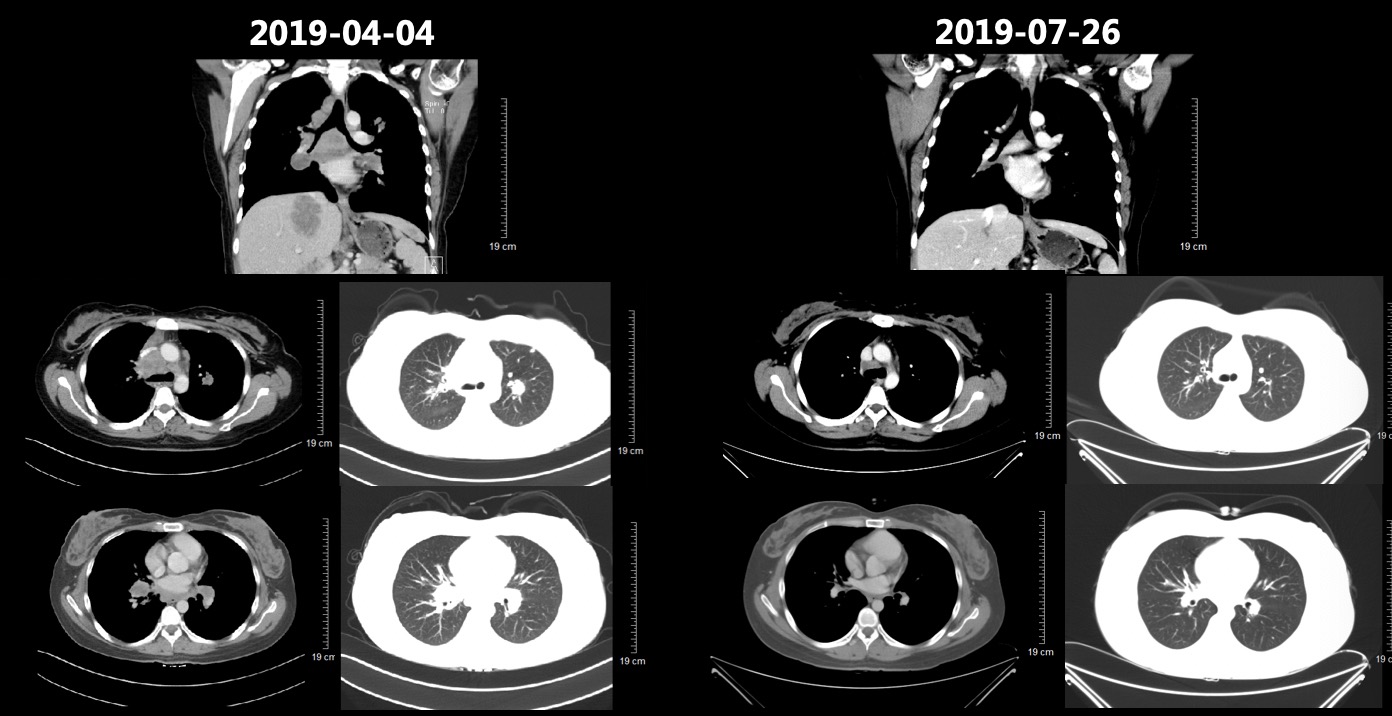

2019-02-19、2019-03-14行二线贝伐珠单抗+多西他赛化疗(贝伐珠单抗+多西他赛,每3周1次)。2019-03患者开始出现腰部疼痛,考虑为L1椎体骨转移导致,2019-03-19开始行腰骶部局部放疗,2019-04-04复查CT结果如图5所示,肺部病灶稳定(部分缩小),肝脏病灶增多增大、T9-T12椎体新发转移瘤,总体疗效评价(PD)。

image011.jpg

图5 2019-04-04复查胸腹部CT结果影像,结果显示肺部病灶稳定(部分缩小),肝脏病灶增多增大、T9-T12椎体新发转移瘤